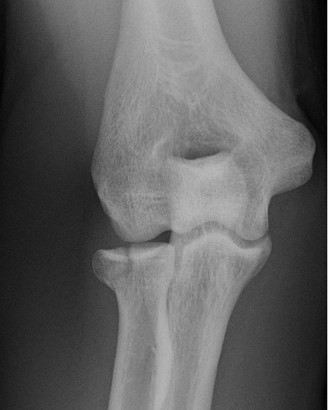

It should be noted that reverse total shoulder arthroplasty is also the procedure of choice in patients with cuff-tear arthropathy (aka rotator cuff arthropathy). Characteristics of cuff-tear arthropathy include superior migration of the humerus due to a massive rotator cuff tear, glenohumeral joint destruction, subchondral osteoporosis, and humeral head collapse (see Fig. 2–17). A reverse total shoulder

Figure 2–17_X-rays of a patient showing evidence of cuff tear arthropathy. The humerus is migrated superiorly, the glenohumeral joint is destroyed, there is subchondral osteoporosis, and the humeral head is collapsed. (From Ecklund KJ, Lee TQ, Tibone J, Gupta R. Rotator cuff tear arthropathy. _J Am Acad Orthop Surg. 2007;15(6):340–349.)